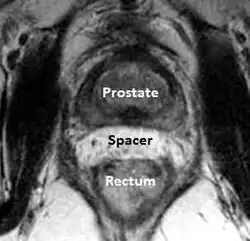

A new method to reduce rectal radiation injury in prostate cancer patients involves the use of an absorbable spacer placed between the prostate and rectum.

Such spacers are commercially available in some regions and are undergoing clinical trials in others.[31] By temporarily altering the anatomy these products have the potential to allow for improved cancer targeting while minimizing risk to neighboring healthy tissues. Prostate rectum spacers should be compatible with all prostate cancer radiotherapy treatments including 3D conformal, IMRT and stereotactic radiation and brachytherapy.